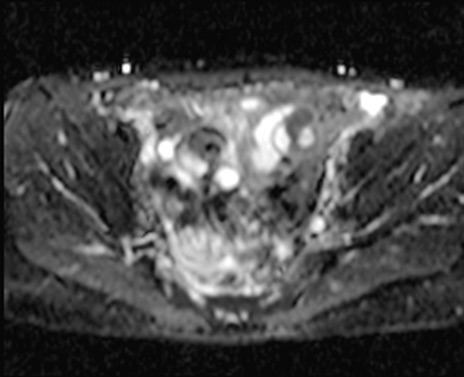

【症例】40歳代女性

【主訴】上下腹部痛

【現病歴】2日目から下腹部痛あり。夜間は痛みで眠れなかった。昨日より上腹部痛と下痢が出現。臥位で痛みは軽快したため、休んでいた。本日になって臥位でも立位でも痛みが強くなってきたため救急要請。

【既往歴】子宮内膜症

【身体所見】部:平坦・軟、左上下腹部に圧痛あり、反跳痛あり。

【データ】WBC 21800、CRP 26.78

MRI(4日後)